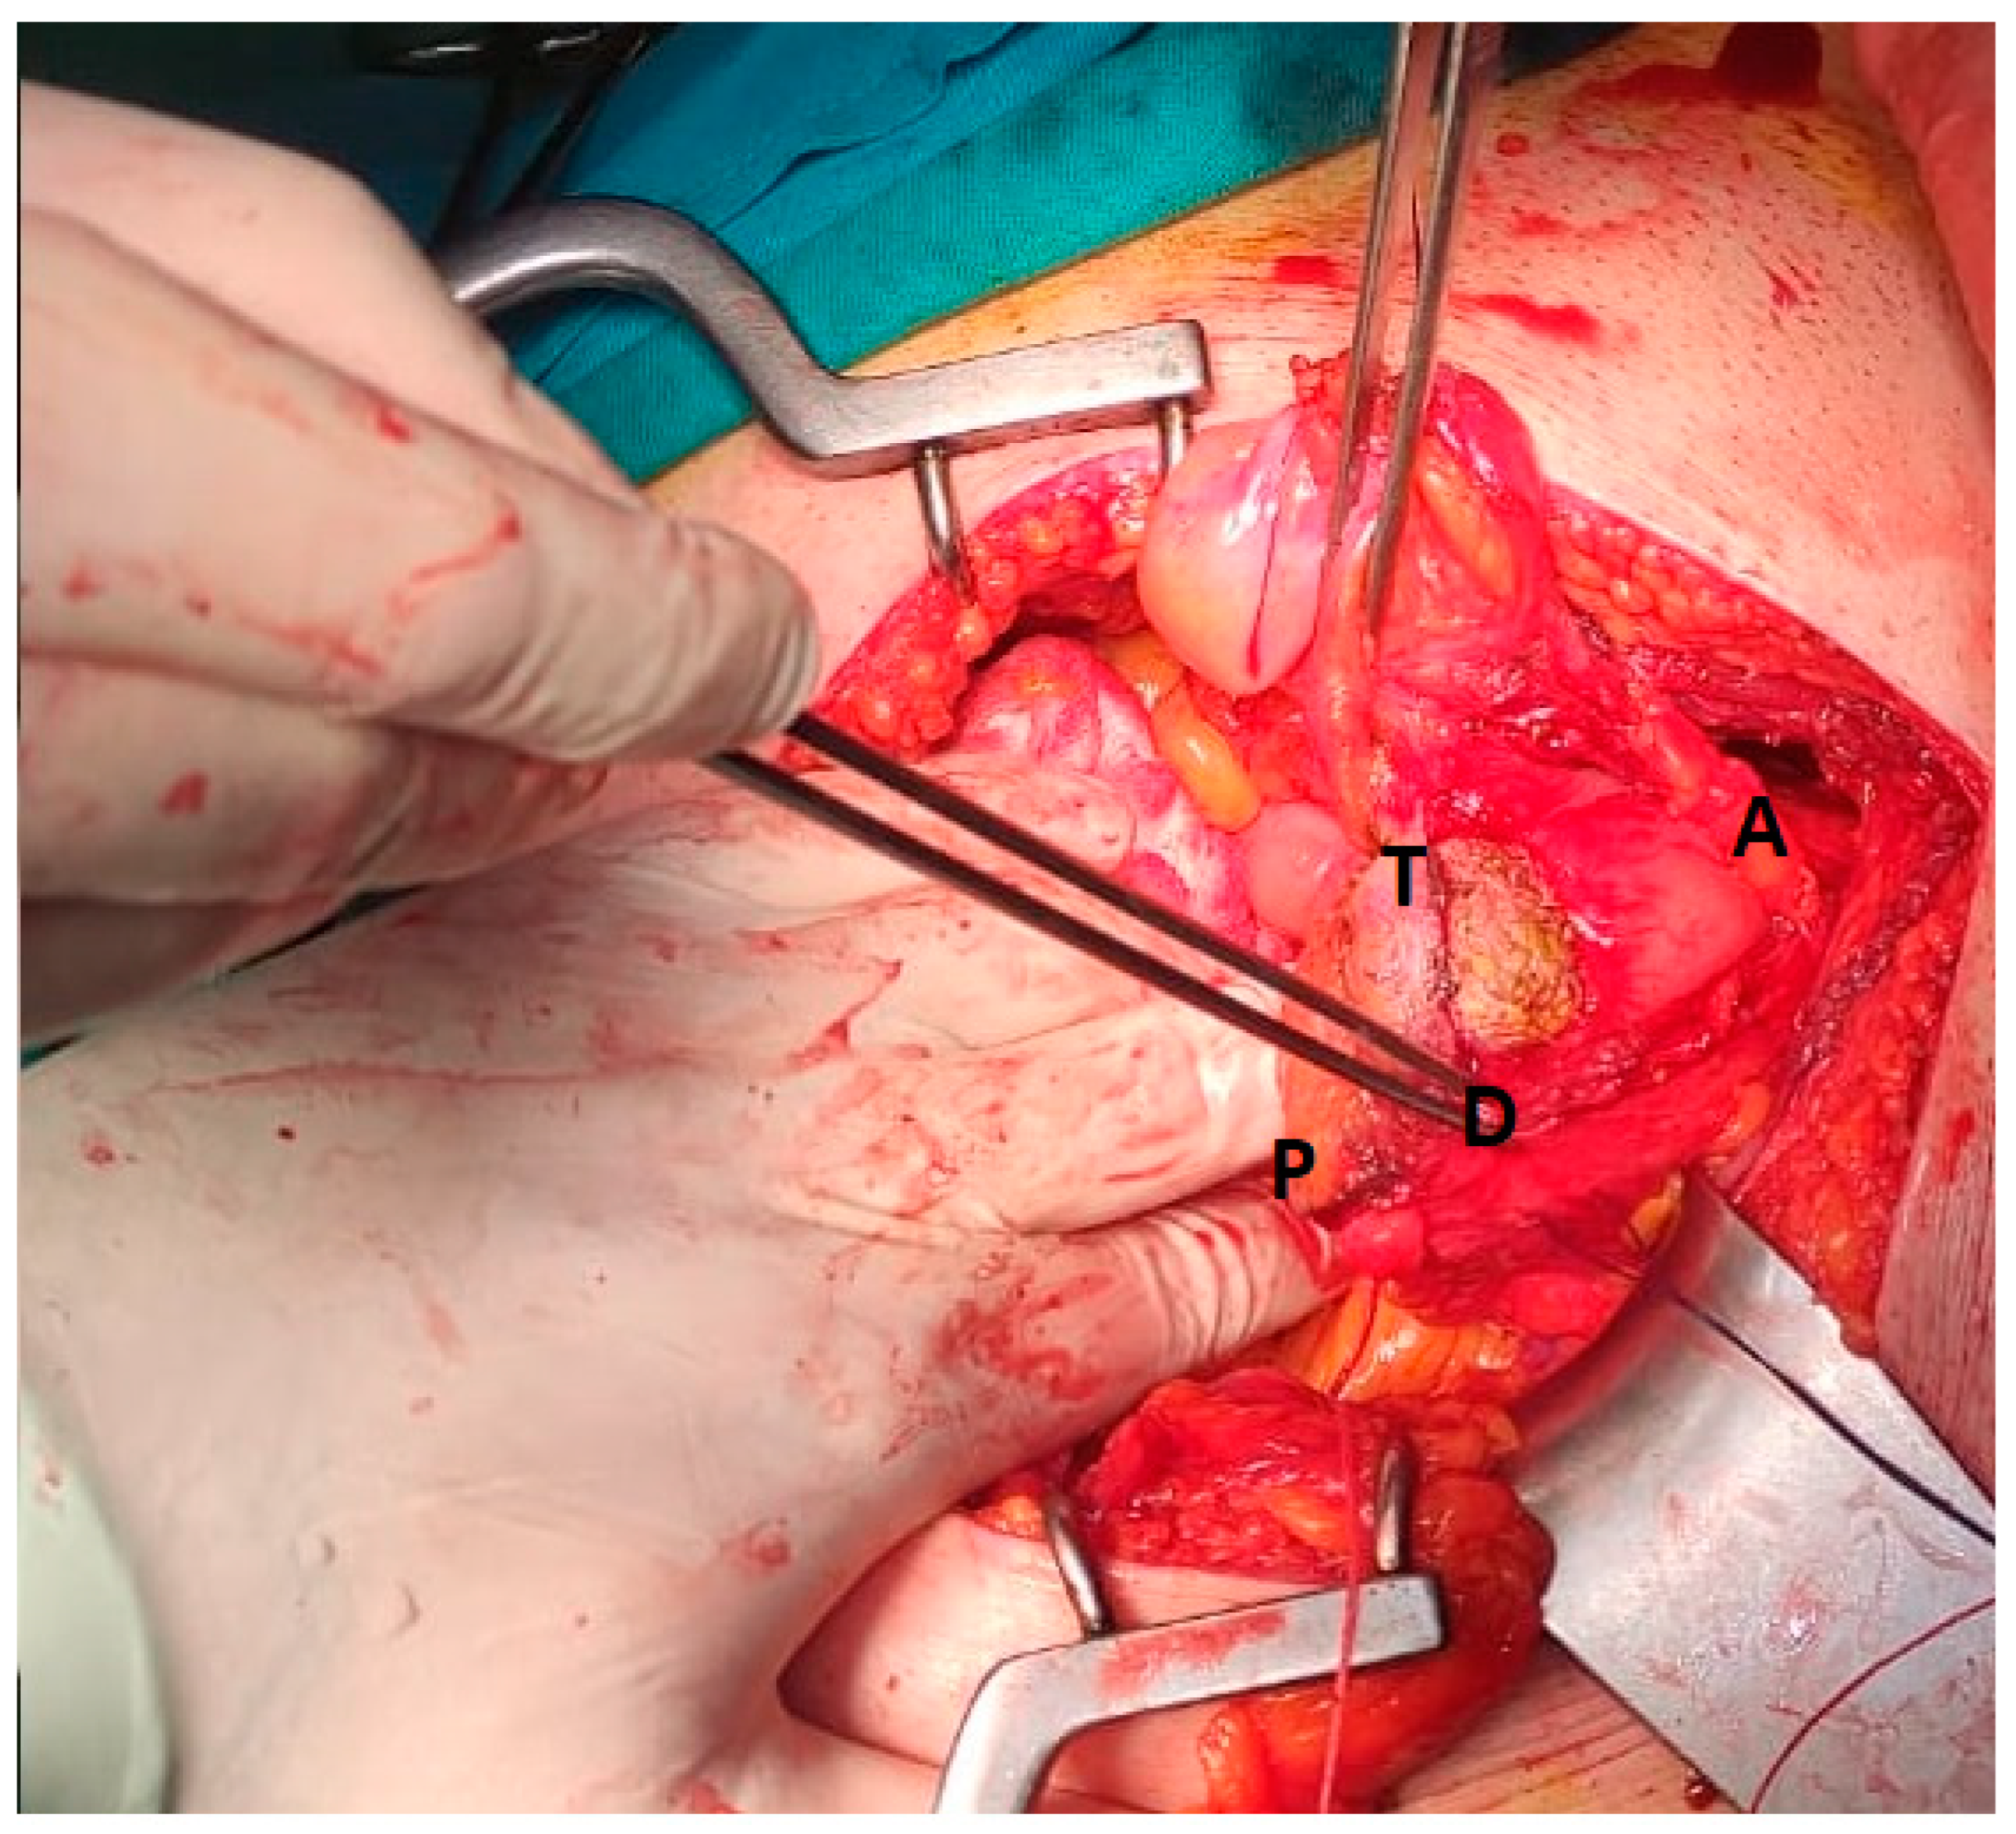

2. Detailed Case Description